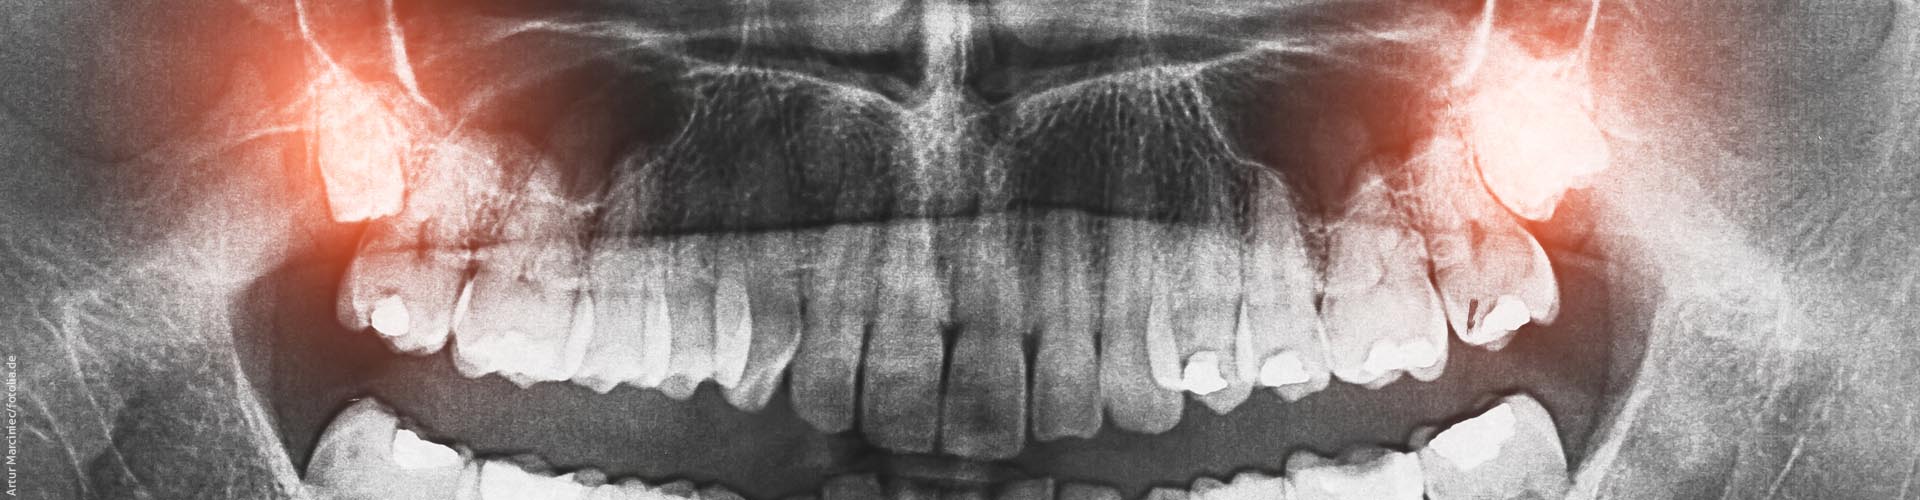

Panoramaaufnahme

Eine Panoramaaufnahme (Orthopantomogramm, kurz OPG) ist eine Übersichtsaufnahme der Zähne und der Kiefer. Auf diesem Röntgenbild lässt sich erkennen:

- ob einer oder mehrere Zähne nicht angelegt sind und im bleibenden Gebiss fehlen werden

- wie die Zähne geformt sind

- wie die Zahnwurzeln im Kiefer liegen ob Weisheitszähne vorhanden sind und ob sie eventuell später entfernt werden sollten

- ob fehlende Zähne möglicherweise vorhanden sind (retinierte Zähne), sie aber z. B. nicht herauswachsen, weil im Kiefer zu wenig Platz ist

- ob noch nicht herausgewachsene Zähne schief im Kiefer liegen (verlagerte Zähne).

Bei Kindern und Jugendlichen sind außerdem schon die sich entwickelnden Zähne im Kiefer sichtbar (die so genannten Zahnkeime). Und es ist zu sehen, wie weit die Zahnwurzeln der bleibenden Zähne bereits gewachsen sind.